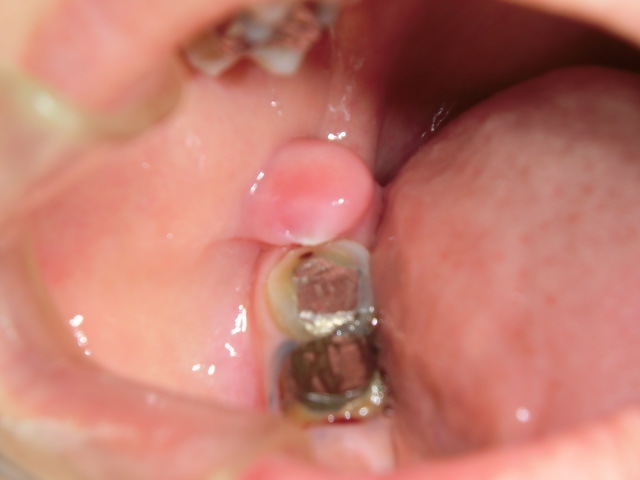

症例1

右下奥歯が治療途中で放置されていました。

おそらくそれが慢性的な機械刺激になってしまったと思われます。